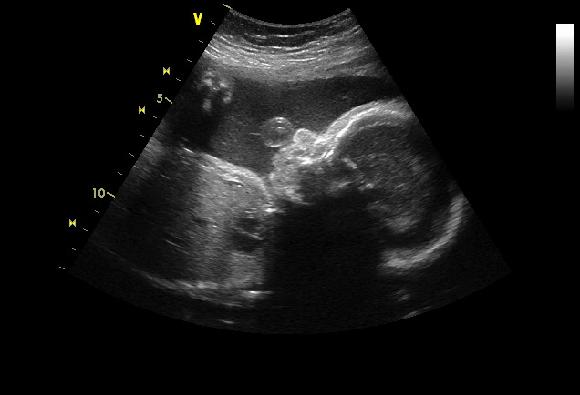

Jinak přikládám foto ze včera.